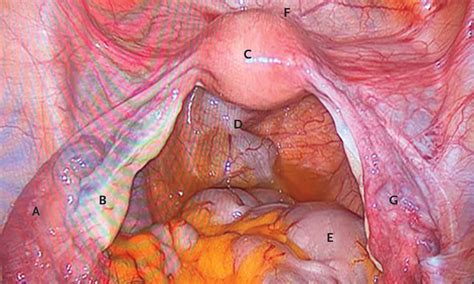

The female reproductive system is composed of several key organs, with the ovaries and fallopian tubes being among the most critical. The ovaries are small, almond-shaped organs located on either side of the uterus. They are responsible for producing hormones and eggs, which are essential for reproduction. The fallopian tubes, also known as oviducts, are a pair of muscular tubes that extend from the upper corners of the uterus to the ovaries. These tubes serve as the pathway for the egg to travel from the ovary to the uterus.

• Laparoscopy: A minimally invasive surgical procedure that allows doctors to view the reproductive organs directly and perform biopsies or repairs if necessary.

In some cases, surgical intervention may be necessary to address more severe conditions. Procedures such as laparoscopy can help diagnose and treat issues such as endometriosis, ovarian cysts, and ectopic pregnancy. Advanced techniques such as in vitro fertilization (IVF) can also be used to overcome fertility challenges.